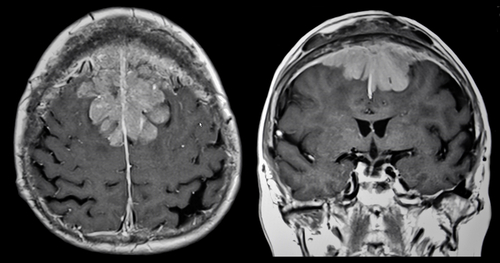

The neurosurgical team of Apollo Cancer Institute here performed the total resection of brain tumor using a new technique Fluorescence Guided Surgery (FGS) on a four-year-old girl child from Assam, recently.

The child is healthy and living pain free after the removal of a life threatening brain tumor 5X5 cms large (size of a tennis ball) that left her with frequent seizures. The girl reported with multiple episodes of drop attack, around 4 to 5 times a day and was diagnosed with a malignant brain tumor Extraventricular Ependymoma, a rare brain tumor that caused walking disorder, balance coordination and repeated seizures.

The Neurosurgery team, who performed the life saving surgery to completely remove the tumor that was buried in the area of her brain causing frequent seizures. In the FGS technique, a special dye is ingested an hour before the surgery, that spreads over the whole body, but the highly active cells (like tumor cells) takes up the dye more as compared to normal cells. When seen under yellow 560 filter (a special filter integrated in the microscope) makes the tumor cells look distinctly different (fluorescence) as compared to normal cells.

This guides the surgeon to clearly distinguish the tumor from the healthy areas minimizing damage to the brain and avoiding post-operative complications.